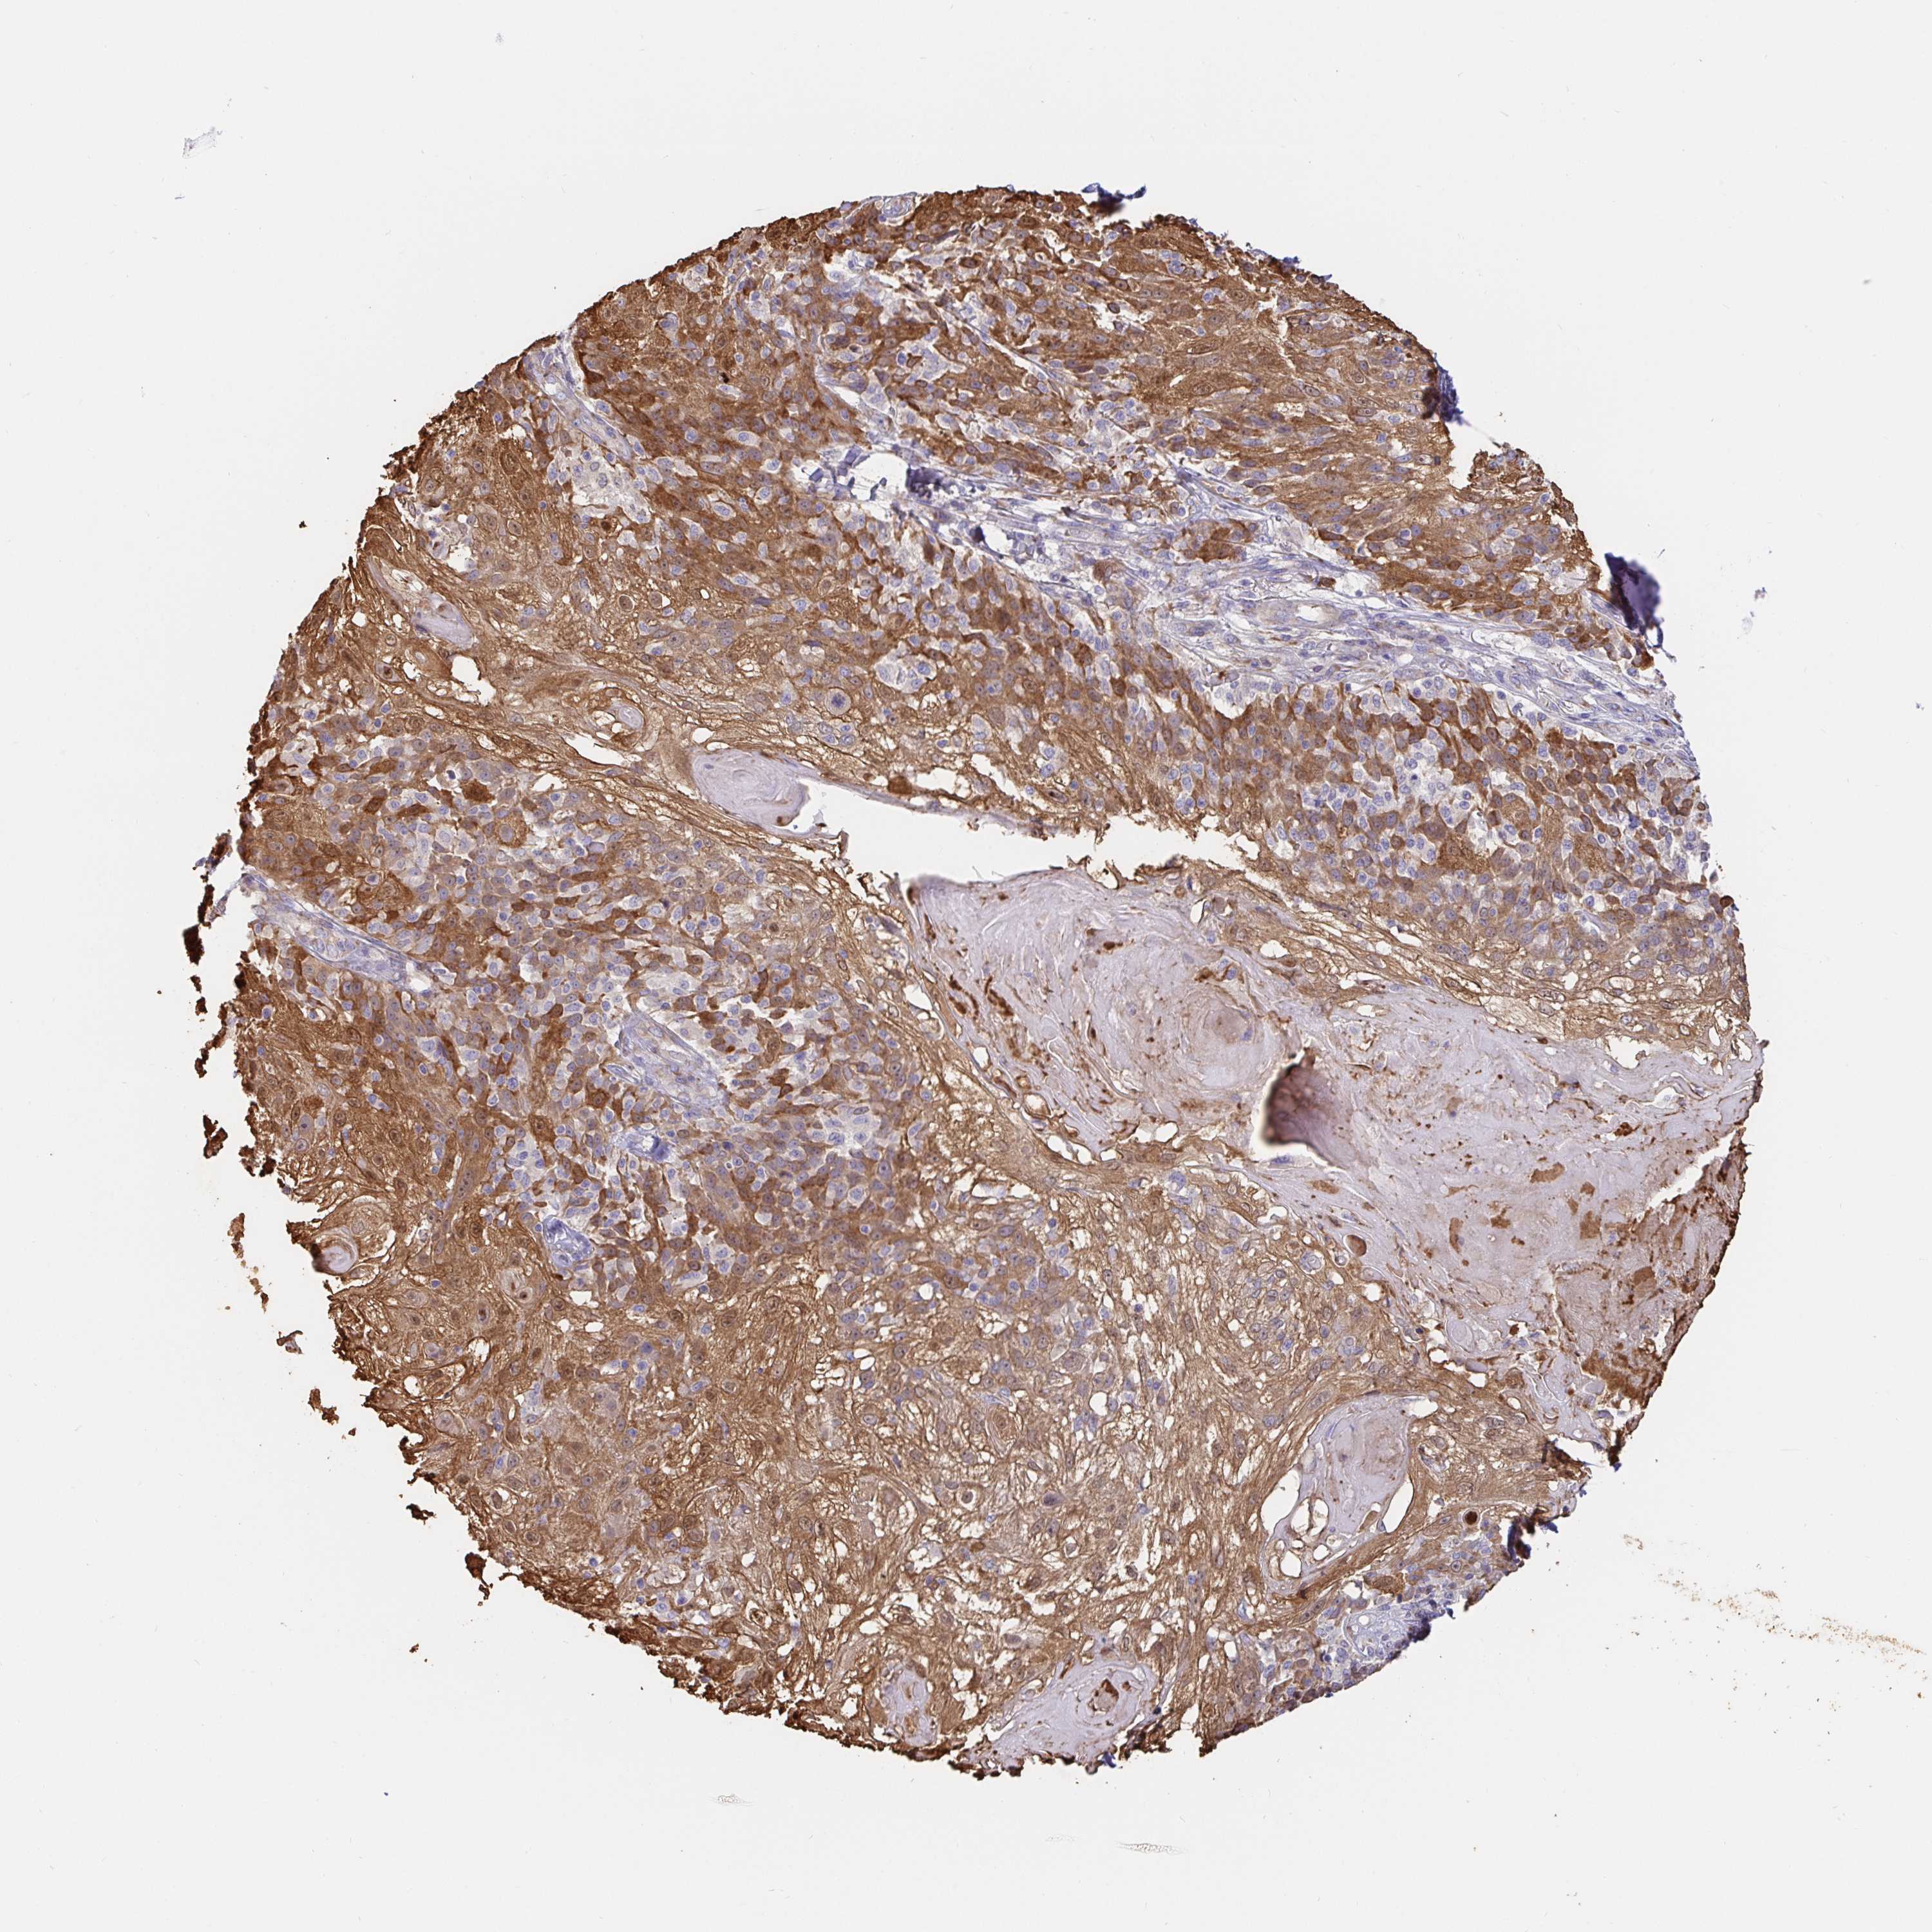

SKIN CANCER - Protein expressioni

A mouse-over function shows sample information and annotation data. Click on an image to view it in a full screen mode. Samples can be filtered based on level of antibody staining by selecting one or several of the following categories: high, medium, low and not detected. The assay and annotation is described here.

Antibody stainingi

Antibody staining in the annotated cell types in the current human tissue is reported as not detected, low, medium, or high, based on conventional immunohistochemistry profiling in selected tissues. This score is based on the combination of the staining intensity and fraction of stained cells.

Each image is clickable and will lead to virtual microscopy that enables deeper exploration of all samples and also displays staining intensity scores, fraction scores and subcellular localization as well as patient and tissue information for each sample.

Antibody HPA035199

Antibody CAB004272

Staining

High

Medium

Low

Not detected

Intensity

Strong

Moderate

Weak

Negative

Quantity

>75%

75%-25%

<25%

None

Location

Nuclear

Cytoplasmic/membranous

Cytoplasmic/membranous,nuclear

Basal cell carcinoma

Squamous cell carcinoma, NOS